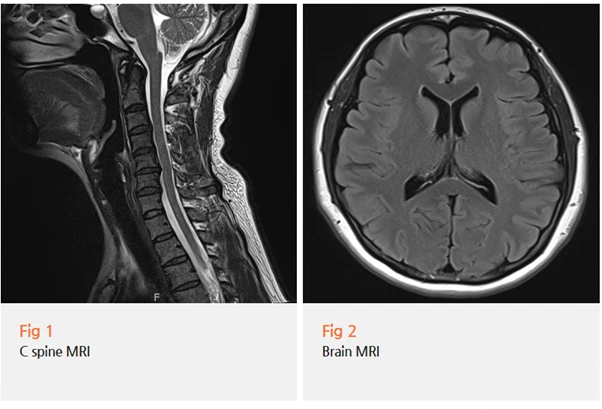

호전이 없었던 점을 고려해 경추 MRI를 먼저 진행했어요.

검사 결과는 예상대로였습니다.

경추 4-5-6번 사이에 협착증이 확인됐어요.

혹시라도 뇌 질환의 영향이 있을까 싶어 추가로 검사한

뇌 MRI에서는 특별한 이상 소견이 없었습니다.